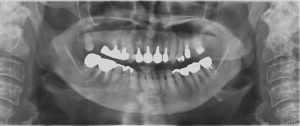

下の写真はインプラントを埋入する前のパノラマ写真です。

写真は左右反転して見て下さい。